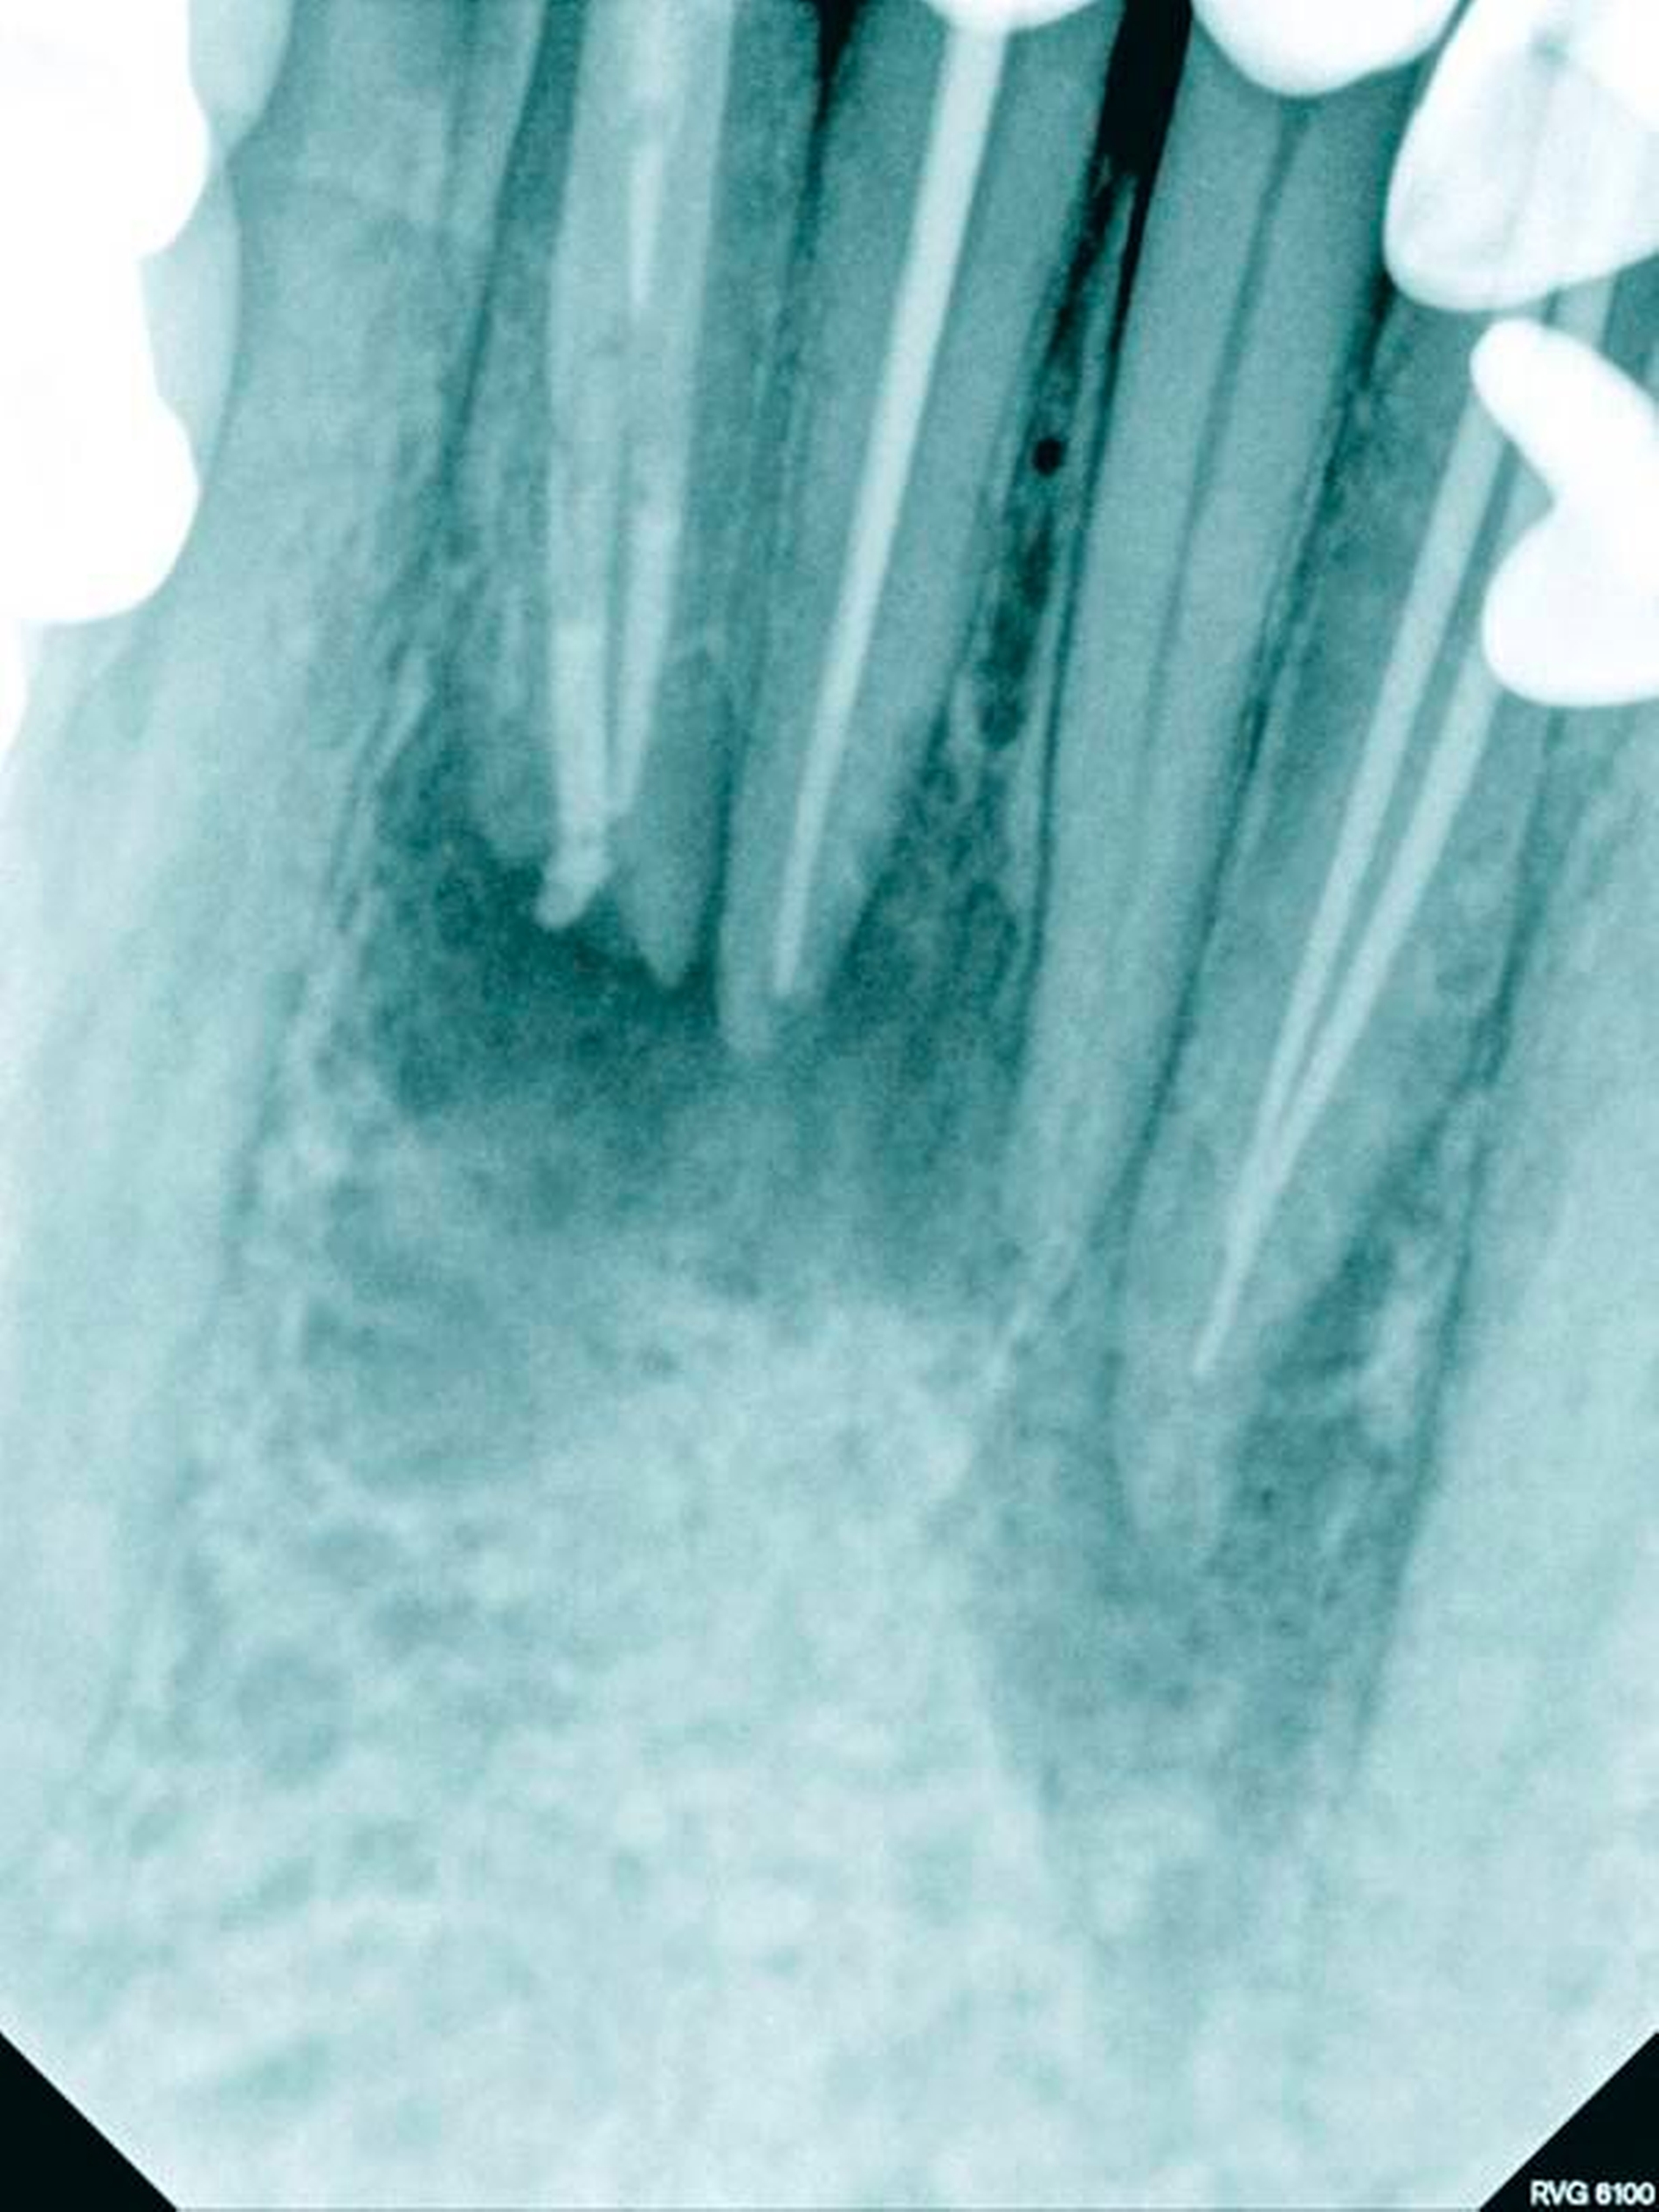

Die geringe Größe der klinischen Zahnkrone mit maximal 4 bis 5 mm Breite oder eine gedrehte oder gekippte Zahnstellung allein sind große klinische Herausforderungen, das Wurzelkanalsystem im Fall einer endodontischen Behandlung vollständig darstellen zu können. Die tiefen Aufteilungen als Folge einer Dentinbrücke lassen sich ohne Nutzung eines Dentalmikroskops nur mit erheblichem Zahnhartsubstanzverlust darstellen, so dass der Langzeiterhalt des Zahnes mit der erhöhten Gefahr einer Vertikalfraktur kompromittiert wird. Bei alters- oder reizbedingten Obliterationen des Wurzelkanalsystems erhöht sich darüber hinaus das Risiko einer lateralen Wurzelperforation oder Instrumentenfraktur [Kvinnsland, 1989] (Abbildungen 16a und 16b).

Die mikrobielle Infektion und die unvollständige Wurzelkanalbehandlung lassen sich durch allein chirurgisch resektive Verfahren nicht korrigieren (Abbildungen 17 bis 20). Sofern eine retrograde Präparation, Desinfektion und ein bakteriendichter Verschluss gelingen, kann die Infektion eingeschlossen werden. Die orthograde Revision im Verlauf der antimikrobiellen Therapie ermöglicht unter mikroskopischer Sicht eine vollständige Reinigung und Desinfektion (Abbildungen 15 bis 17).